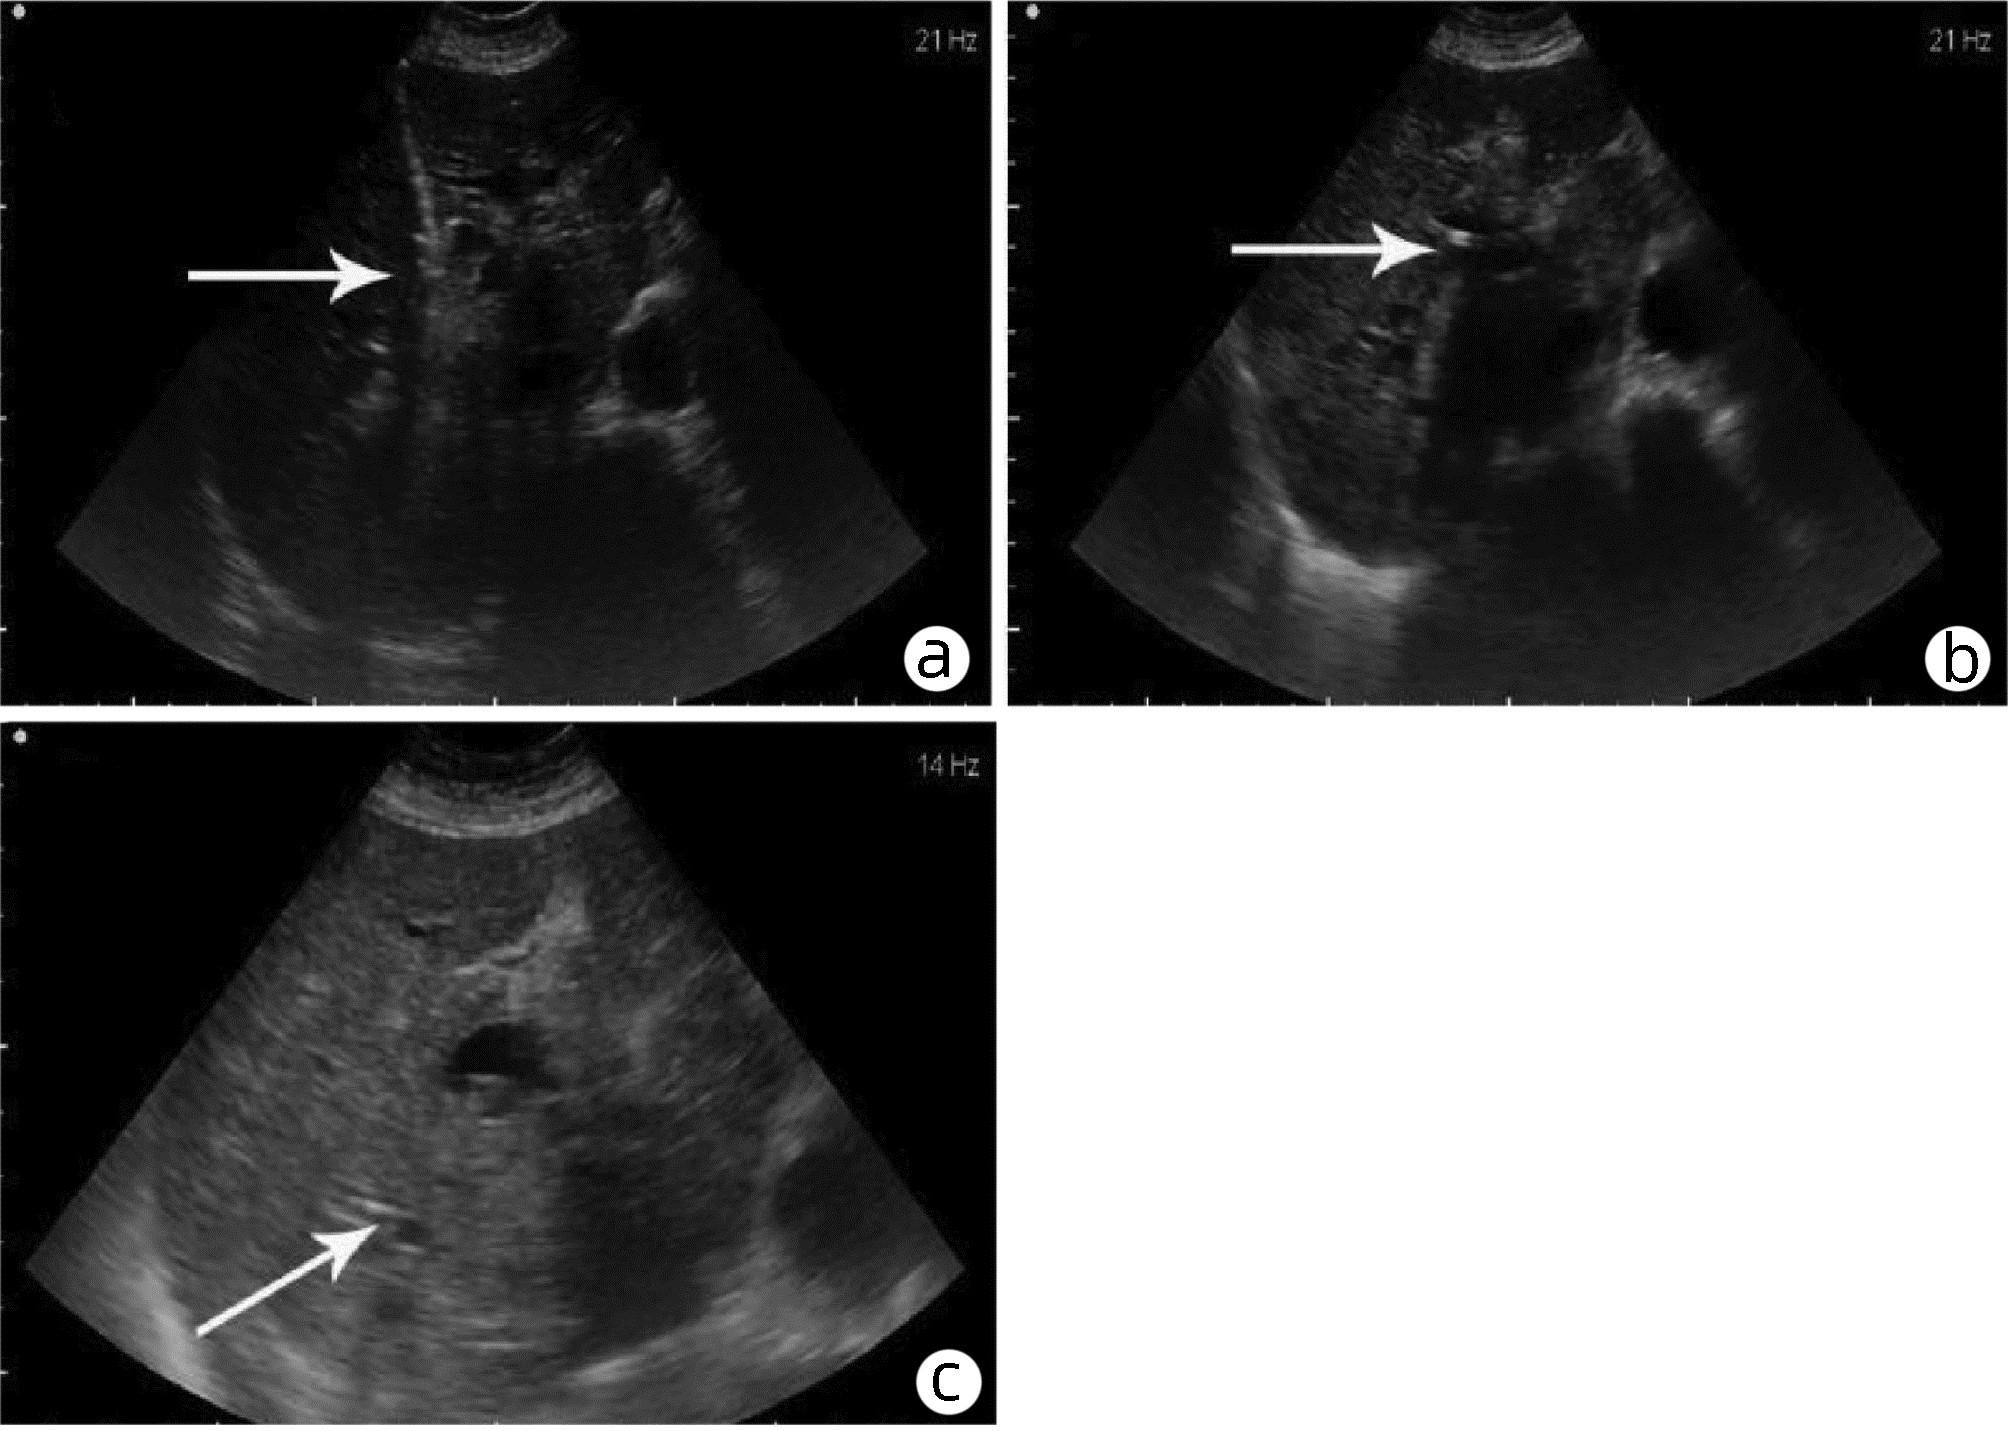

Application and clinical evaluation of ultrasound-guided biliary drainage tube replacement technology

Anhong ZHANG, Ruixin ZHANG, jie MA, Bo QIU, Xin YI, Zhihua LU, Lijie ZHENG, Hanguang DONG, Tian HAN, Li ZHANG, Yuanhui JIANG, Jun XU

2022, 38(11): 2542-2545. DOI: 10.3969/j.issn.1001-5256.2022.11.020

Abstract(1345) HTML (380) PDF (1987KB)(53)

Abstract:

Objective  To summarize the preliminary application results of ultrasound-guided biliary drainage tube replacement, present the corresponding technical points, and discuss the operation strategy and clinical application value.  Methods  The clinical data of 60 patients who underwent ultrasound-guided biliary drainage tube replacement in Qilu Hospital of Shandong University between August 2014 and August 2020 were retrospectively analyzed. The operation procedure, clinical applications, and postoperative complications were summarized and analyzed.  Results  Fifty-eight of the 60 patients (96.67%) were successfully replaced with drainage tubes along the original sinus. Among them, dilated sinus tracts of 47 patients were placed with coarse-grade drainage tubes, and dilated sinus tracts of the remaining 11 patients were placed with the original type of drainage tubes, with the mean operation time of 15.8(12.0-19.0) min under local anesthesia. In total, bile was drained from 28 patients receiving PTCD drainage, 23 patients receiving gallbladder drainage, and 9 patients receiving T-tube drainage. The post-operation evaluation revealed that the drainage situation has improved, with a 100% effective rate. No obvious abnormality was found in the postoperative follow-up visit.  Conclusion  The replacement of drainage tube under ultrasound guidance is simple, safe and feasible, and it provides further promotion in clinical practice with sufficient data support.